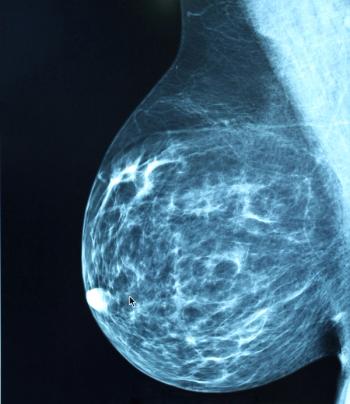

Novel therapies could potentially expand the population of patients with ERBB2-positive metastatic breast cancer who experience long-lasting disease response, according to a review in JAMA Oncology.

A quality improvement study in JAMA Network Open has found that a significantly lower percentage of patients with breast cancer presented with stage I disease before the COVID-19 pandemic, in 2019, compared to after the start of the pandemic, in 2020.